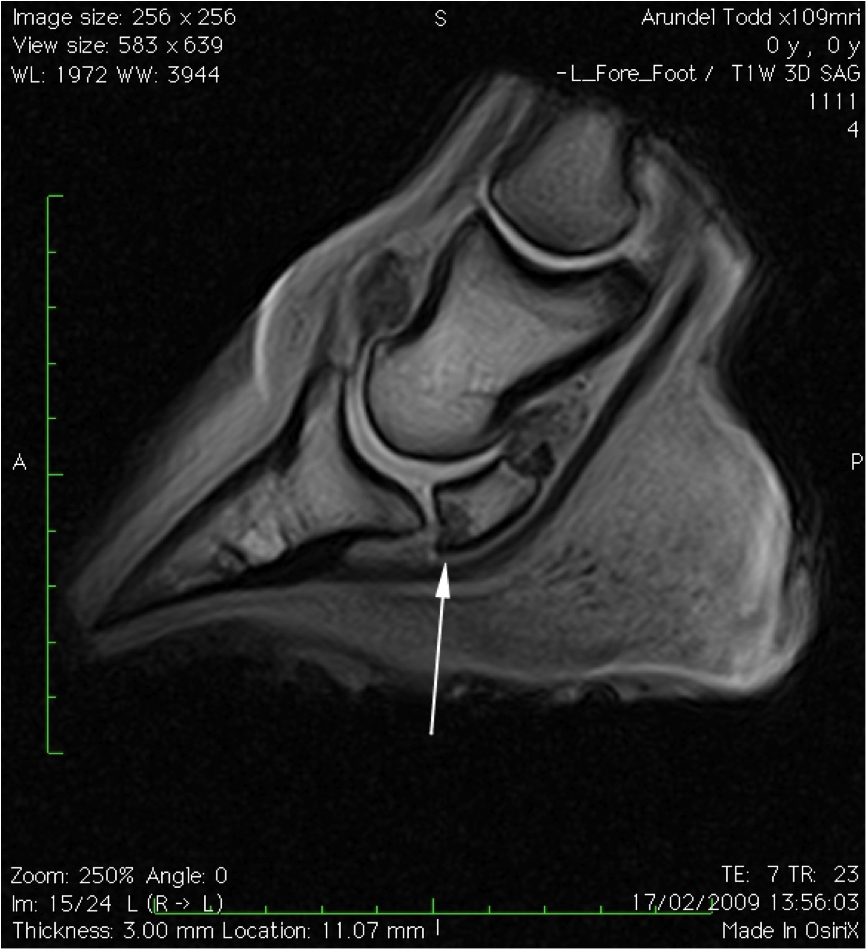

December Navicular Cyst Swiftsure Equine Bone Spur On Navicular Horse Horse now shod with raised heels/short. The paired suspensory navicular ligaments originate from the dorsolateral and dorsomedial aspects of the proximal phalanx and attach to the proximal navicular border and both extremities. Xrays show spur on nb probably impeding tendon. Navicular syndrome is a degenerative disease complex of horses that can encompass injuries to any of the structures within the. Bone Spur On Navicular Horse.

Navicular syndrome causes, diagnosis and treatment Vet Times Bone Spur On Navicular Horse The navicular bone is held in position by three strong ligaments. Xrays show spur on nb probably impeding tendon. Navicular syndrome is a degenerative disease complex of horses that can encompass injuries to any of the structures within the navicular apparatus of the foot, including the navicular bone, navicular bursa, collateral sesamoid ligaments, distal impar ligament, or deep digital flexor. Bone Spur On Navicular Horse.

Figure 7 from Navicular syndrome in equine patients anatomy, causes Bone Spur On Navicular Horse Navicular bone partition is a rare condition reported in horses, which is during the evaluation of a lameness or prepurchase. Navicular in horses relates to problems associated with the navicular bone in the horse’s hoof and is a common diagnosis for lameness in the front foot. Xrays show spur on nb probably impeding tendon. Navicular syndrome is a degenerative disease. Bone Spur On Navicular Horse.